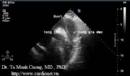

Nghiên cứu chức năng tâm trương thất trái và thất phải bằng siêu âm Doppler tim (Luận án Tiến sỹ Y học của TS. Tạ Mạnh Cường - Full text)